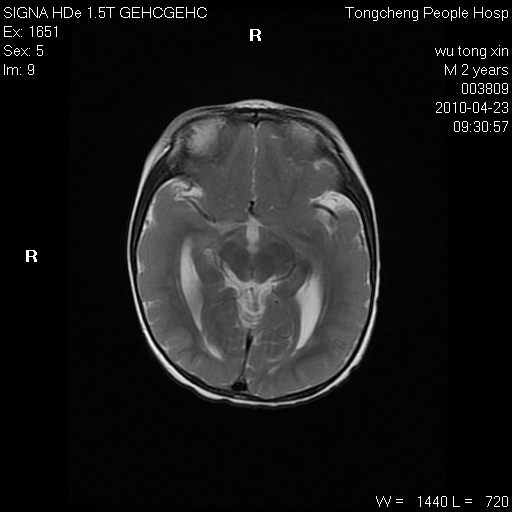

以下是引用赵物学在2010-4-25 12:43:00的发言:[br]巨脑回[br]侧脑室后角低密度影考虑hie或肾上腺脑白质营养不良?[br][br][本贴已被 赵物学 于 2010-4-25 12:51:28 修改过]

以下是引用gaoxiao在2010-4-25 16:54:00的发言:[br]巨脑回畸形。脑白质髓鞘化不良

以下是引用pujunzhi在2010-4-25 21:35:00的发言:[br]考虑 1双侧大脑皮质发育不良 2轻度脑积水 3双侧脑室后角旁片状长t1长t2信号,需继续观察,因为正常小儿此处脑白质的髓鞘化时间可以延迟到4-6岁,才显示正常。